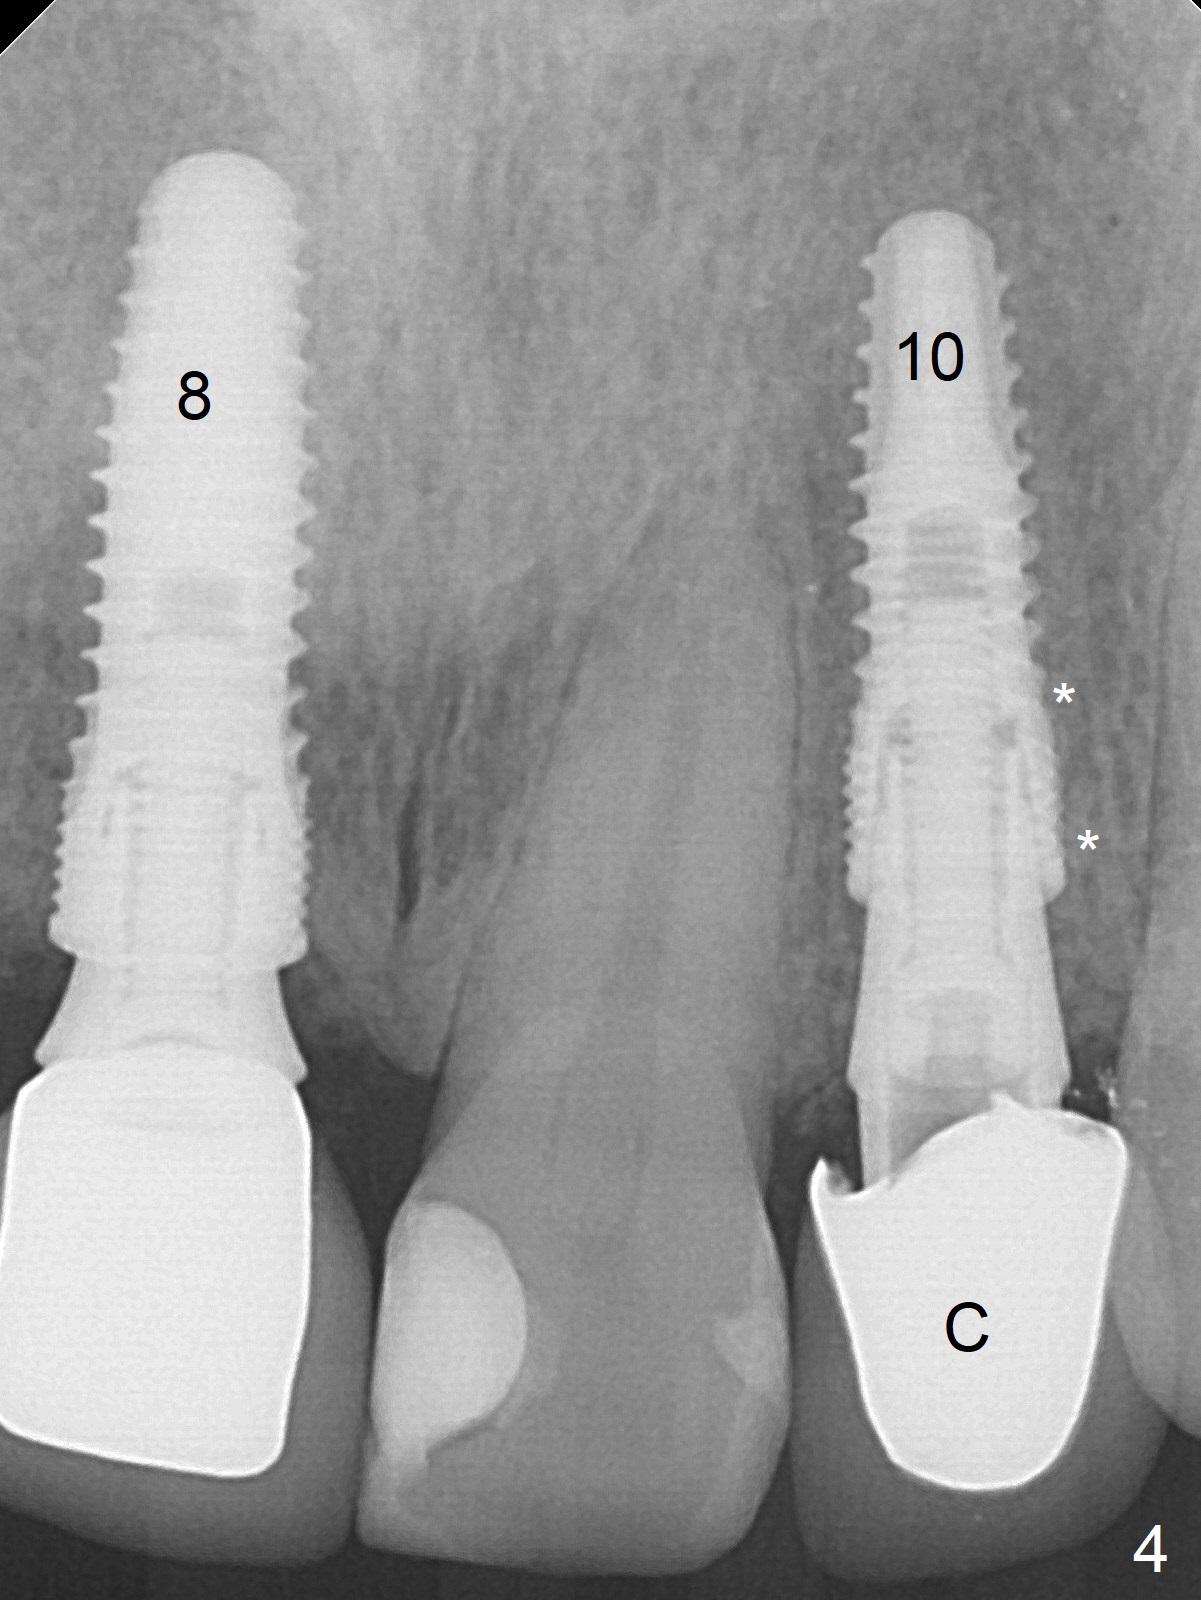

When the patient returns, the crown at #10 has displaced incisally (Fig.1,2 arrow). The initial depth is 15 mm (Fig.3, palatal gingival margin). After a 3.8x12 mm SM implant is placed (Fig.4), allograft is packed in the peri-implant space (*, as compared to Fig.3) and a 3.9x4(3) mm abutment is placed (A). More allograft is placed in the peri-abutment space (Fig.6 *). The existing crown (Fig.4,5 C) is hollowed, relined (R) and used as an immediate provisional (Fig.7-9). The patient is pleased with the appearance of the apically-repositioned provisional (Fig.7 arrow). She returns for impression 3.5 months postop (Fig.10). After change of abutment to 3.9x4(4.5) mm and new provisional, impression is retaken 5 months postop (Fig.11,12). It appears that the implant is palatally placed and a little large for the site (Fig.11 (B: buccal); Fig.12 (^: thin layer of the palatal plate)). If an angled abutment were used, a screw-retained crown might have been feasible. Due to the new provisional, the gingiva looks healthy when a permanent crown is cemented (Fig.13).